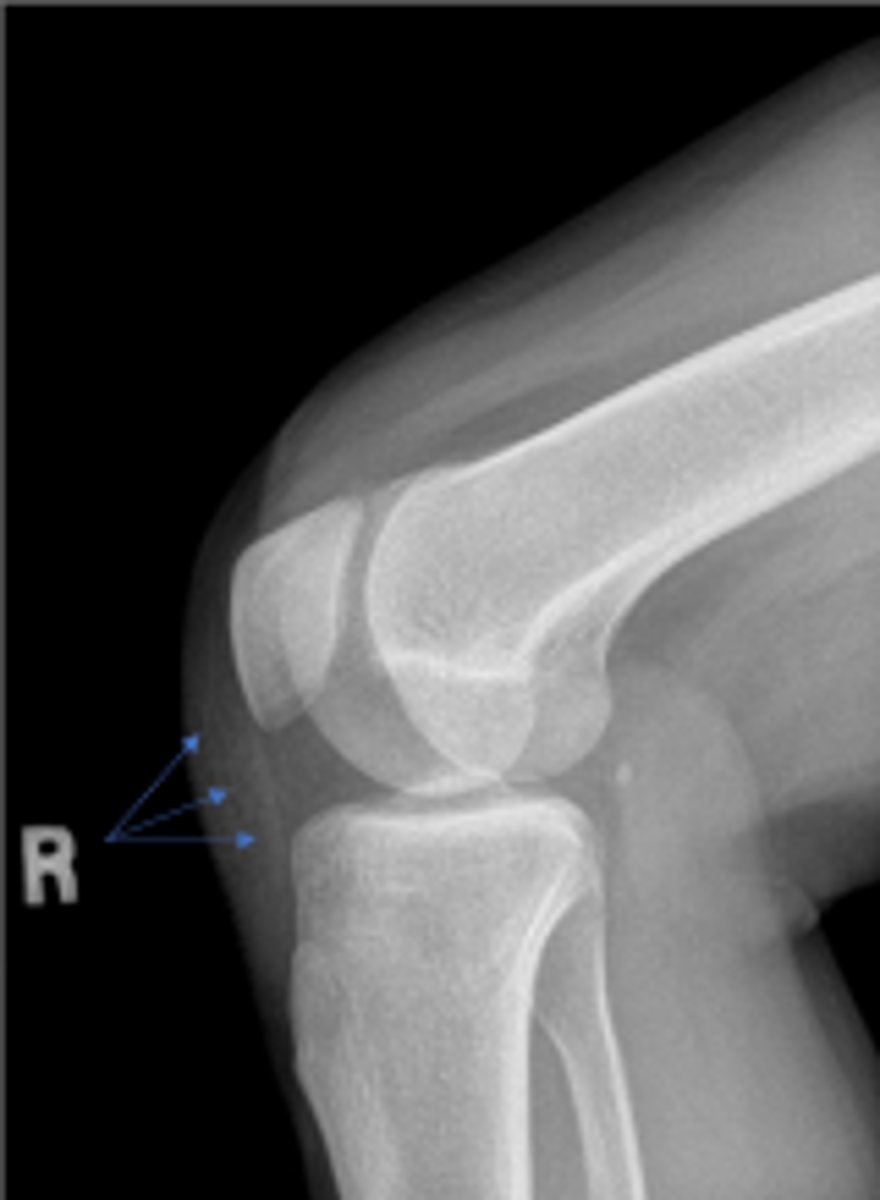

What is the name of the radiographic view?

Right internal oblique knee

Right proximal tibiofibular joint space

What space are the arrows pointing to?